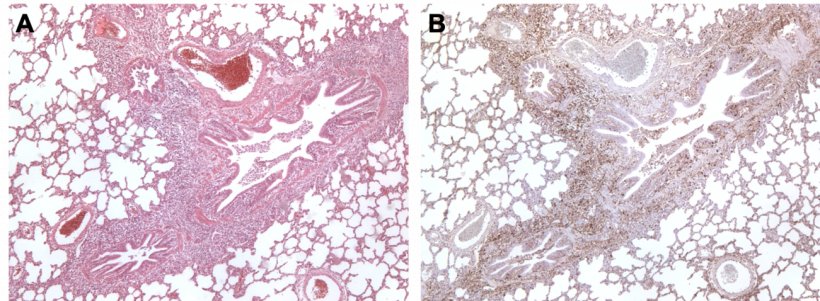

Dans le cas de la co-infection M. hyopneumoniae et PCV2, il a été constaté que M. hyopneumoniae augmente la gravité des lésions produites par le PCV2 dans les organes pulmonaires et lymphoïdes, favorisant une plus grande réplication du virus, ainsi que la persistance de celui-ci dans les tissus (figure 3), augmentant ainsi l'incidence des cas de circovirose systémique (le nom qui reçoit actuellement le processus de la MAP (appelé PMWS, de l'anglais Postweaning Multisystemic Wasting Syndrome).

Figure 3. Poumon d'un porc co-infecté par M. hyopneumoniae et PCV2. A: Zone d'hyperplasie lymphoïde péribronchiolaire causée par M. hyopneumoniae. B: Grande quantité d'antigène PCV2 dans la même zone d'hyperplasie lymphoïde.